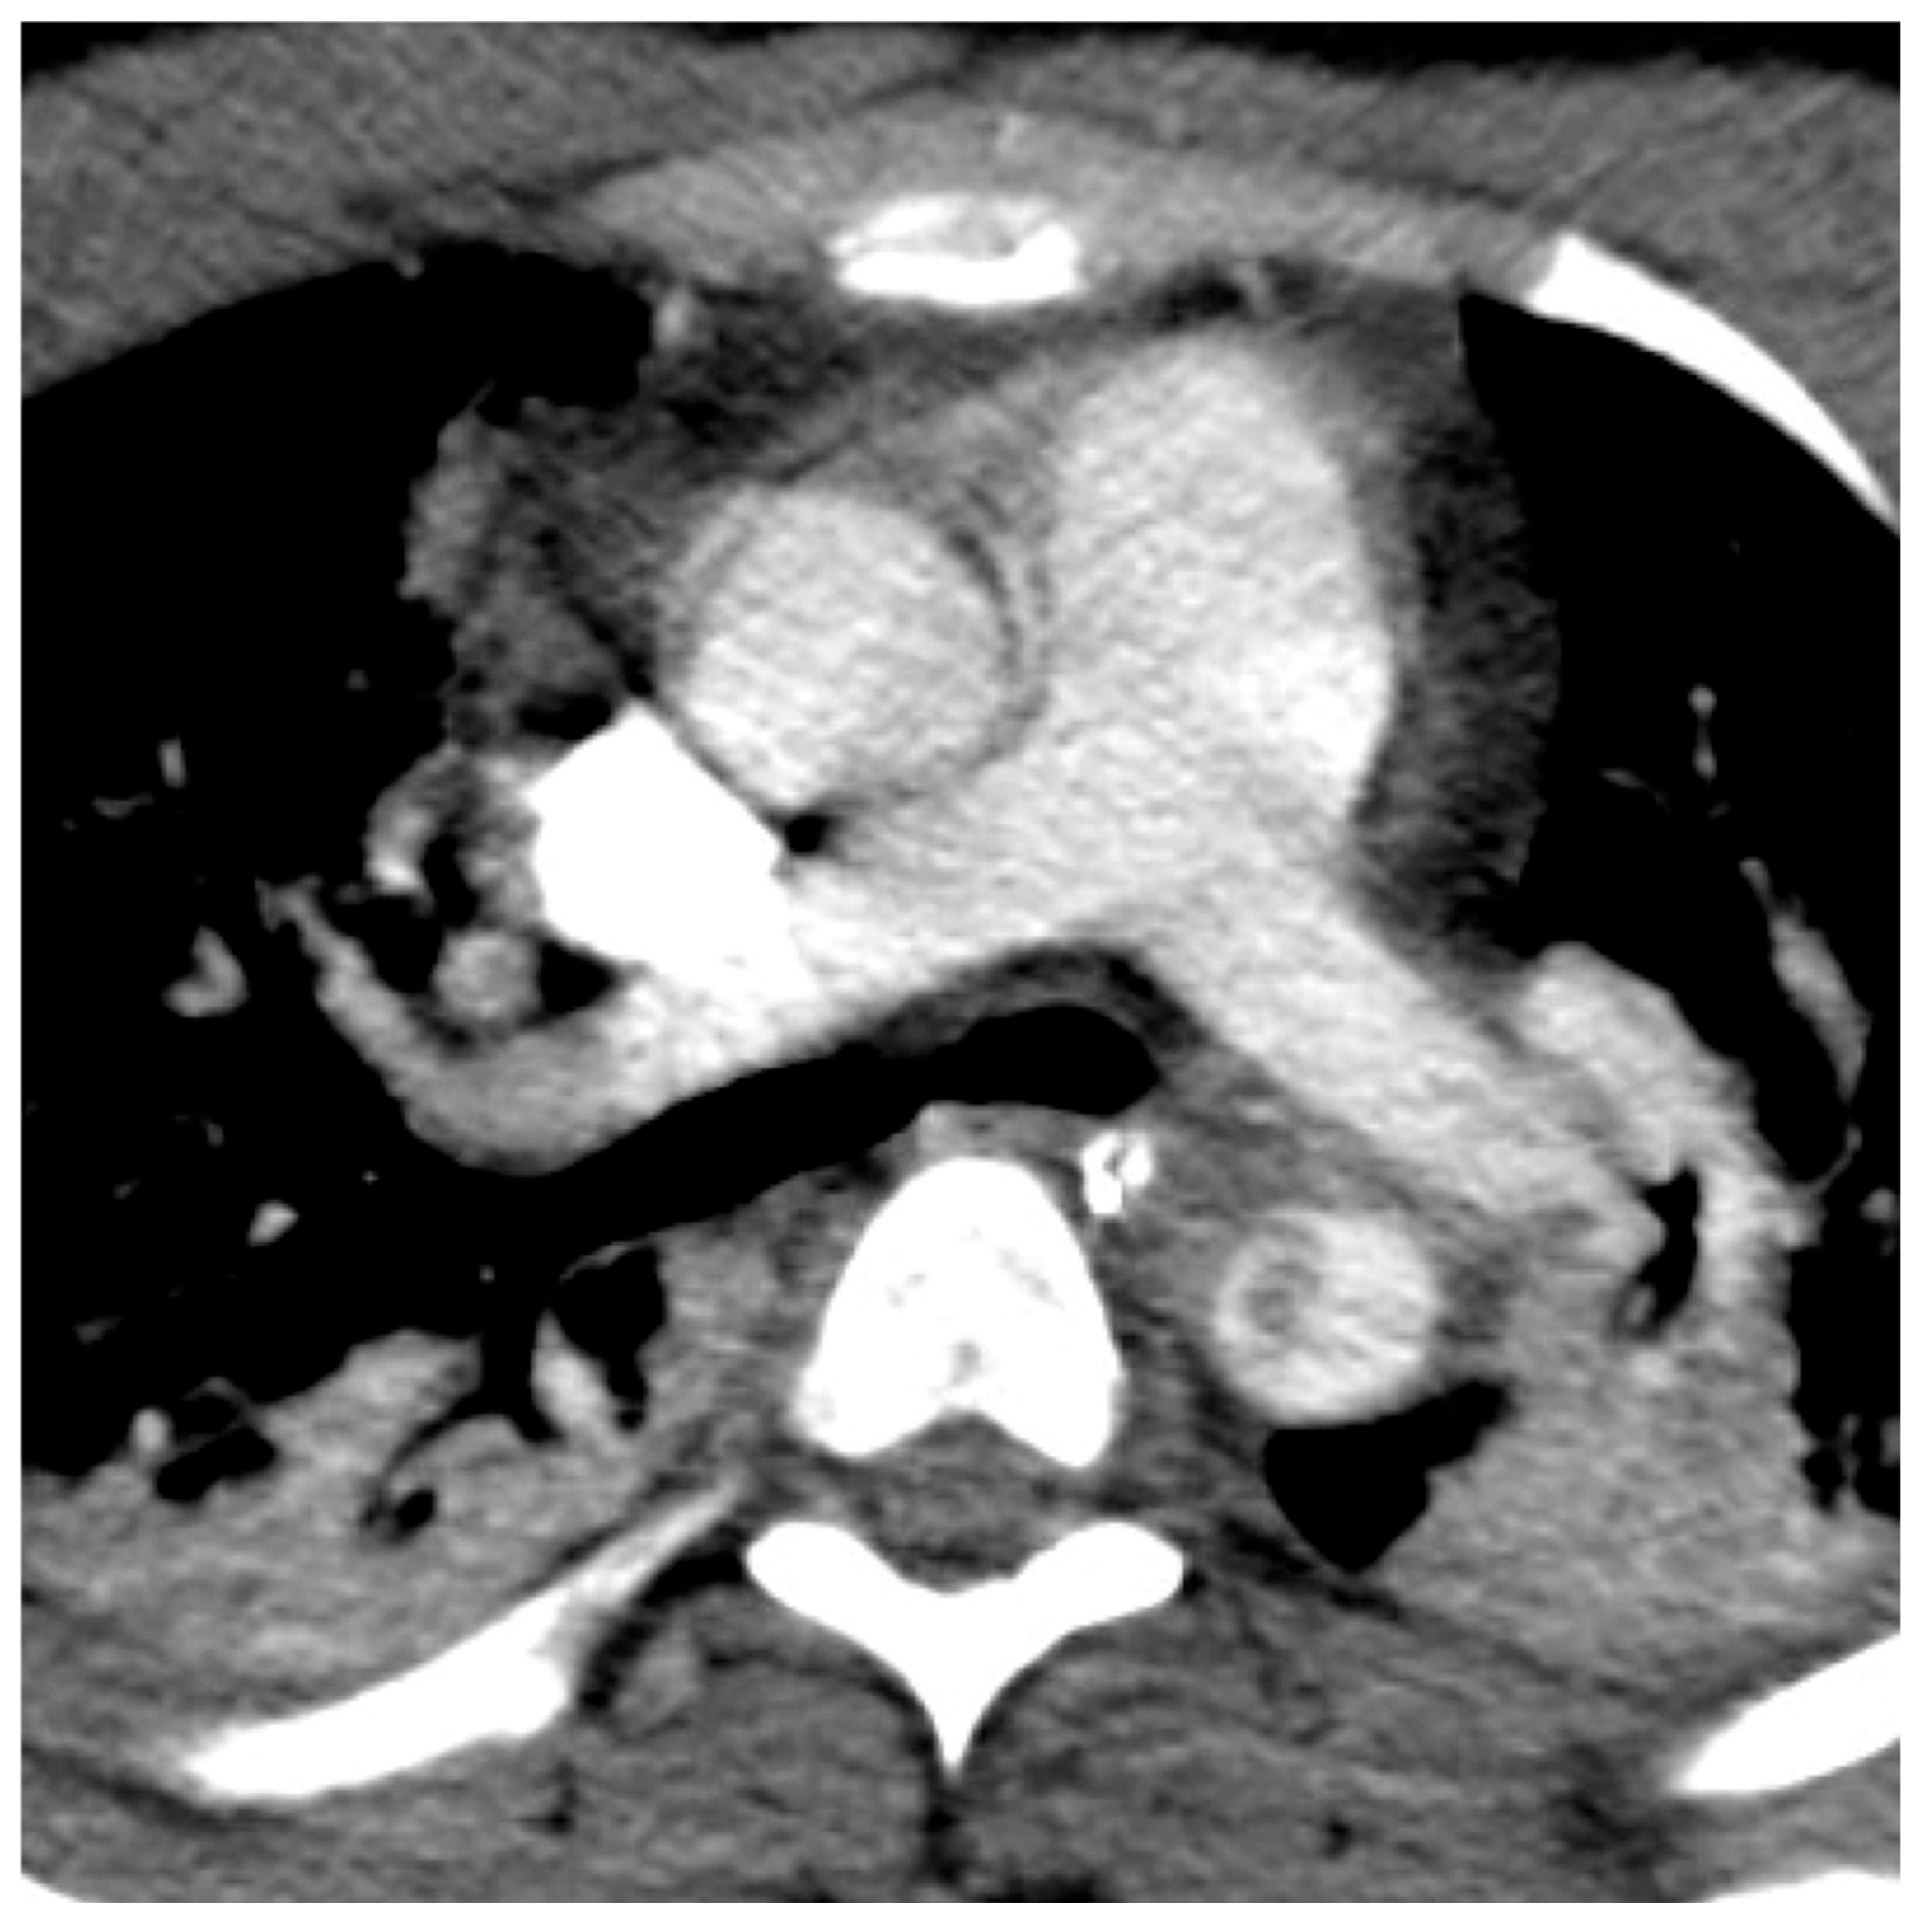

| 2 (focal dissection/intramural hematoma) | 10 (26%) |